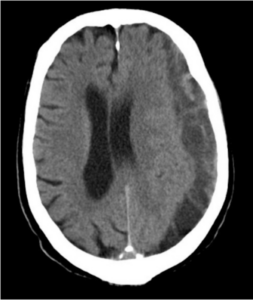

慢性硬膜下血腫は頭部外傷後1〜2ヶ月経って、脳の表面(硬膜下腔)にサラサラの血液がゆっくり溜まって脳を圧迫する疾患です。特に高齢の方、お酒をよく飲む方、血液をサラサラにする薬を飲んでいる方に起こりやすく、軽く頭をぶつけた程度の外傷でも起こることがあります。血腫の量が多いと脳の圧迫が強くなり、片方の手足の動かしにくさ、歩きにくさ、頭痛、認知症など、様々な症状がみられるようになります。これらの症状はゆっくりと現れるため「歩くのが遅くなった」「少し物忘れが増えた」といった変化に気づきにくいこともあります。血腫が小さい場合は自然に吸収されることもあります。しかし血腫が大きくて脳を圧迫し、上記のような症状が出ている場合は治療が必要です。治療は主に手術で、頭蓋骨に小さな穴を開けて血腫を吸い出す手術が行われます。手術を受けると麻痺などの症状は良くなり、後遺症は残らないことが多いです。